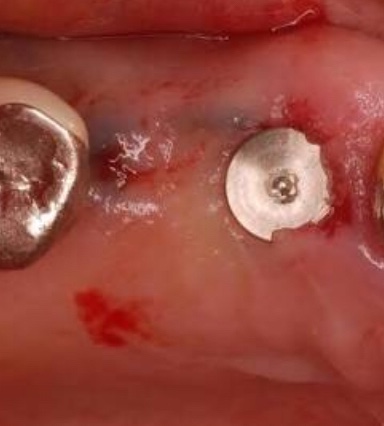

手術後にこの段階の写真をみせてくれたのだが、まるで歯茎に井戸のような丸い穴がポッカリとできていた。

チタン埋め込みと縫合

穴あけ後の写真撮影後、チタンを埋め込んでいったが、これは痛くもかゆくもなく、特に問題なく平常心で処置をうけることができた。

これも埋め込み後に写真撮影をして、術後に写真をみせてもらったところ、井戸に円柱形のものが埋められており、うえからみると、まるでマンホールの蓋のようにみえた。

写真はイメージです